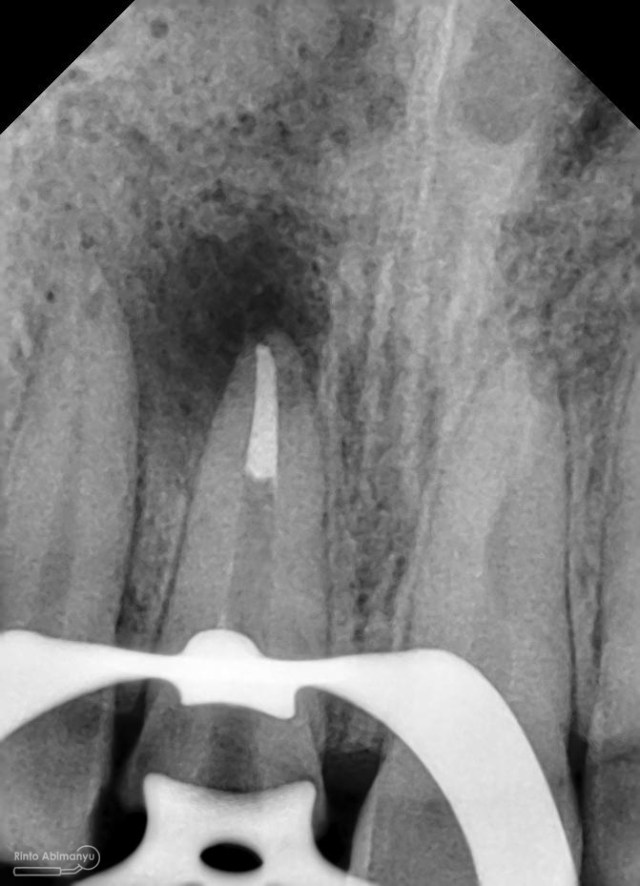

dan ini foto ronsen nya…

Foto radiografis gigi 11 21 22 yang mengalami fraktur

Kemudian dilakukan pengepasan guttap dan difoto ronsen….

Foto radiografis trial guttap

Dari ronsen terlihat guttap sudah pas dan langsung hari itu juga saya lakukan pengisian saluran akar kemudia pasien pulang…. Pada saat selesai pengisian tidak saya lakukan ronsen lagi karena saya merencanakan ronsen evaluasi pengisiannya sekalian foto ronsen saat pengepasan guttap pada gigi 22 saja biar efektif…